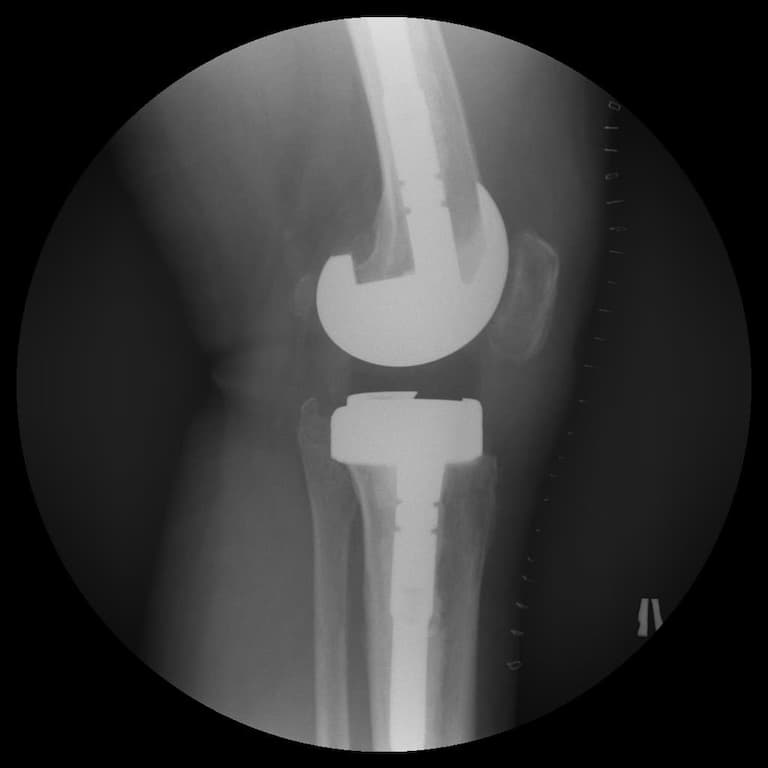

Үе дайрсан ясны анхдагч хавдар, ясны дутмагшлын үед хийгдэх мэс засалimage7

Зураг 4. Мэс заслын дараах рентген зураг

Өвчтөний ерөнхий биеийн байдал хурдан сайжирч, шарх эдгэрсэн, хүндрэл тохиолдоогүй.